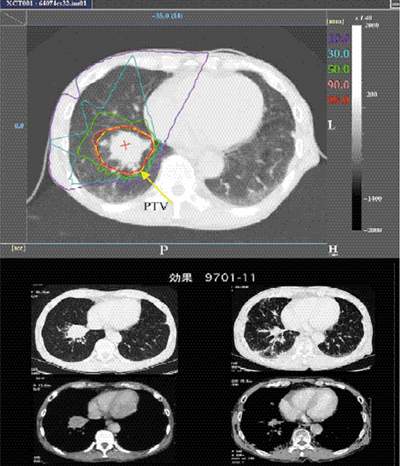

| Облучение g-квантами | Облучение протонами |

| Вид лучевой терапии |

Локализация дозы | Лечению поддаются | |

| g от e Ee≈20 МЭв + IMRT |

хорошая | + | - |

| протоны | отличная | + | - |